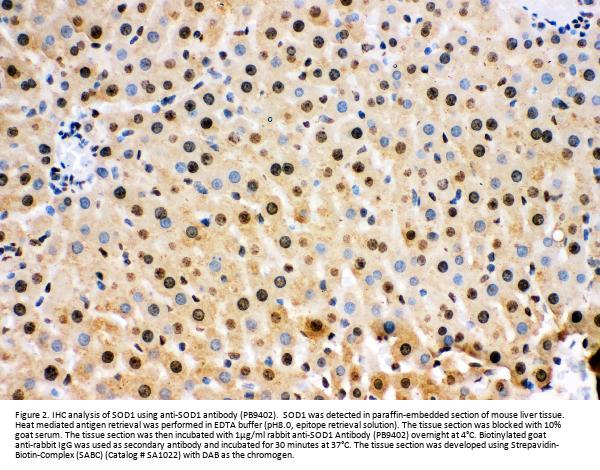

Immunohistochemistry(Paraffin-embedded Section), 2-5 μg/ml, Human

Boster Bio Anti-Superoxide Dismutase 1/SOD1 Antibody Picoband® catalog # PB9402. Tested in Flow Cytometry, IHC, WB applications. This antibody reacts with Human, Mouse, Rat. The brand Picoband indicates this is a premium antibody that guarantees superior quality, high affinity, and strong signals with minimal background in Western blot applications. Only our best-performing antibodies are designated as Picoband, ensuring unmatched performance.